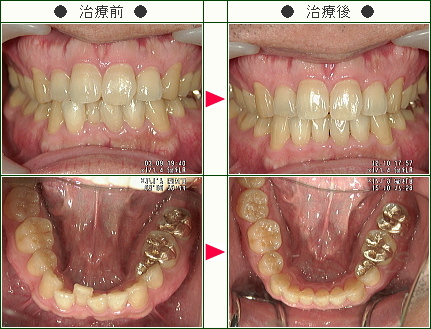

☆デコボコ症例(華 華様 52歳 女性)

▼患者様の感想

長い間のコンプレックスをわずか1年で実現させて頂けたことに感謝しています。

治療中、ほとんど誰にも気づかれなかった事が本当に嬉しい。

残念ながら、少し歯が変色した事があり(今はだいぶ元に戻りましたが)不安に感じたことも事実ですが、全体的にはいつも親身にいろいろアドバイスして頂いたと思っております。

痛みも考えていたよりも重くなくすみ、それよりも笑顔を褒められるようになった事が嬉しいです。

ありがとうございました。